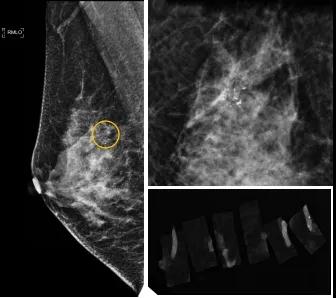

小到1—2mm的鈣化也能活檢!西安國際醫(yī)學(xué)中心醫(yī)院采用精準(zhǔn)技術(shù)讓乳腺早癌無處可逃

46歲的某女士在西安國際醫(yī)學(xué)中心醫(yī)院體檢時(shí),行乳腺X線攝影(俗稱鉬靶)發(fā)現(xiàn)右乳可疑簇狀鈣化,分布范圍不到1厘米,臨床觸不到,超聲很難發(fā)現(xiàn),但是這種鈣化風(fēng)險(xiǎn)比較高,依據(jù)國際BI-RADS指南需要明確病理!

西安國際醫(yī)學(xué)中心醫(yī)院影像診療中心陳寶瑩副主任帶領(lǐng)的團(tuán)隊(duì),采用全數(shù)字化乳腺X線三維立體定位系統(tǒng)可實(shí)施。這個(gè)團(tuán)隊(duì)的成員大部分來自知名三甲醫(yī)院,有著十余年影像引導(dǎo)下乳腺介入診療的經(jīng)驗(yàn),X線引導(dǎo)穿刺定位和活檢例數(shù)居西北前列。為減少患者創(chuàng)傷,在詳細(xì)判讀了患者資料,并與患者及甲乳外科劉曉敏主任充分溝通的基礎(chǔ)上,團(tuán)隊(duì)確定采用全數(shù)字化乳腺X線三維立體定位系統(tǒng)下實(shí)施粗針活檢。

當(dāng)天,乳腺X線三維立體定位系統(tǒng)清晰顯示出了所有鈣化。為了獲取充足的組織量,保證病理診斷的準(zhǔn)確性,團(tuán)隊(duì)選用14G穿刺針并多點(diǎn)、多角度取材,組織取出后,又立即在高清標(biāo)本攝影系統(tǒng)中進(jìn)行投照,從而確定了取出組織中具有足夠的可疑鈣化。整個(gè)過程患者無任何不適,活檢結(jié)束后即回家觀察。

后期病理回報(bào)活檢組織條中均查見導(dǎo)管原位癌。該女士及家屬對西安國際醫(yī)學(xué)中心醫(yī)院早期發(fā)現(xiàn)并精準(zhǔn)確診病變的技術(shù)給予了高度的贊揚(yáng)。

乳腺導(dǎo)管原位癌屬于早期的腫瘤性導(dǎo)管內(nèi)病變,有發(fā)展為浸潤性癌的傾向,需要早發(fā)現(xiàn)早治療,其預(yù)后明顯優(yōu)于浸潤性癌。2020年癌癥雜志的文章指出,近90%的導(dǎo)管原位癌僅表現(xiàn)為不可觸及的可疑鈣化,乳腺X線檢查是發(fā)現(xiàn)微小鈣化最敏感的方式,因此70–90%的導(dǎo)管原位癌是通過乳腺X線篩查發(fā)現(xiàn)。多年來國內(nèi)外指南,如美國國家綜合癌癥網(wǎng)絡(luò)(NCCN)指南及中國抗癌協(xié)會(huì)乳腺癌診治指南均建議40歲以上女性每年通過雙乳X線檢查(鉬靶)進(jìn)行乳腺癌篩查,高危人群建議提前進(jìn)行篩查(小于40歲)。由于雙乳X線篩查的推廣,歐美等國家導(dǎo)管原位癌的檢出率極大提高,明顯降低了乳腺癌的死亡率。在我國規(guī)范進(jìn)行乳腺X線篩查的人群比例比較低,很多人發(fā)現(xiàn)腫瘤時(shí)已經(jīng)為浸潤性癌,因此提醒大家高度重視規(guī)范的雙乳X線篩查。通過乳腺X線篩查發(fā)現(xiàn)的可疑鈣化需要在X線引導(dǎo)下精準(zhǔn)定位,進(jìn)行粗針穿刺或真空輔助旋切活檢,以獲得準(zhǔn)確的病理學(xué)結(jié)果,給予及時(shí)有效的治療。